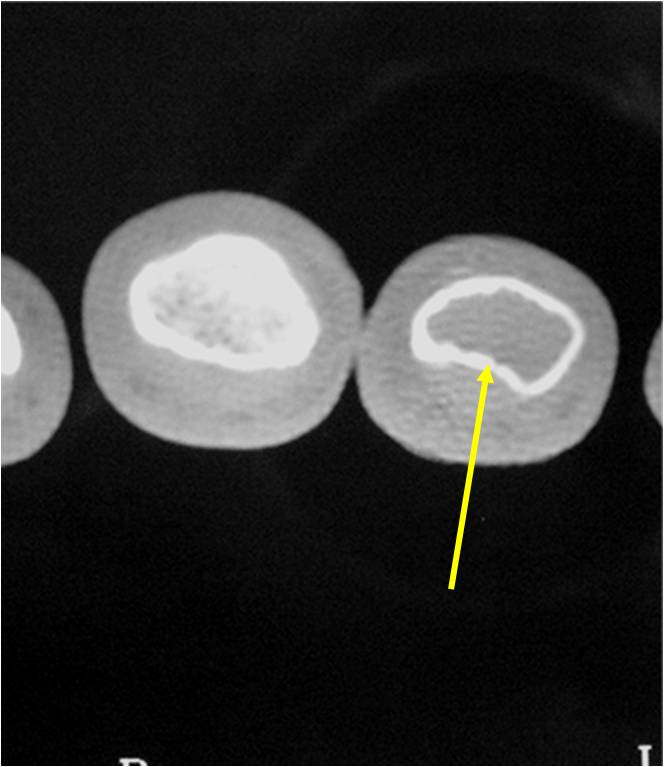

Radiographic Presentation

- Localized, radiolucent defect usually with punctate calcifications

- Calcifications are typical but not always present

- Matrix may demonstrate various degrees of calcification

- Calcifications are stippled, punctate, popcorn like calcifications and “Ring and Arc” calcifications

- Cartilage tumors grow in a lobular manner. The perimeters of the lobules undergo

- enchondral ossification that may calcify. If the entire perimeter of the lobule calcifies it appears

- radiographically as a “Ring”. If a portion of the perimeter of a lobule calcifies it forms an “Arc” on

- an X-ray.

- May be located centrally or eccentrically

- Grows eccentrically or concentrically (phalanges)

- Cortex may be scalloped and thinned in the phalanges

- MRI is better to see noncalcified chondroid lesions and the full extent of lesions

- Most commonly found in metaphysis

Plain X-Ray:

- Geographic lytic lesion

- Central often metaphyseal in long bones

- Can be eccentric also

- Expansile remodeling with thinned cortex

- Chondroid matrix with calcifications in majority of tumors

- Approximately 20% have limited or no calcifications

- There should never be any cortical destruction nor a soft tissue component. If this exists then the tumor must be a chondrosarcoma.

- Endosteal scalloping and cortical expansion is acceptable for phalangeal tumors. In most benign long bone cartilage tumors there is minimal endosteal scalloping but there should be no cortical expansion nor thickening. There should be no cortical destruction and no soft tissue component associated with an enchondroma. Cortical destruction, periosteal thickening, cortical expansion and a soft tissue component indicates a chondrosarcoma of the long bone.

Ring and Arc Calcifications Minimal Endosteal Scalloping Cortex Intact No Soft Tissue Component No Periosteal Reaction

Ring and Arc Calcification No Endosteal Scalloping

Metaphyseal Tumor Heavy Calcifications Ring and Arc Pattern of Calcifications Minimal Endosteal Scalloping No Cortical Destruction No Periosteal Reaction No Cortical Destruction No Soft Tissue Component

- Endosteal erosion>2/3 cortical thickness on a CT scan